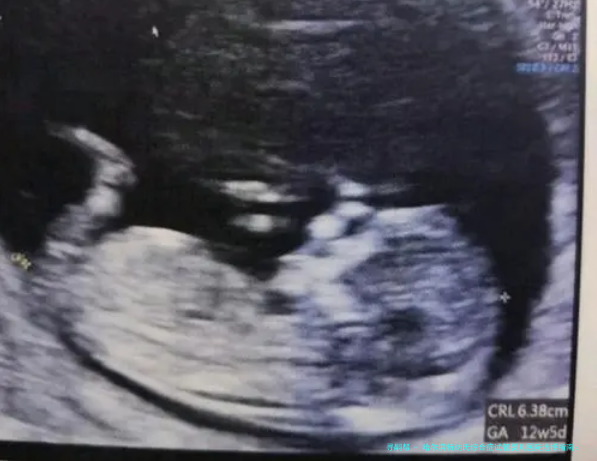

对于得了特纳氏综合症的夫妻来讲,选择一家适当的试管婴儿医院是实现生育愿望的重要一步。特纳氏综合症(Turner Syndrome)病人由于染色体异样,自行受孕概率偏低,时常需要借助辅助生殖技术。哈尔滨作为东北地区的医疗中心,具有多家在辅助生殖医学范畴病症凸起的医院。本文将给您详细介绍哈尔滨地区在特纳氏综合症试管婴儿治疗方面受欢迎程度较高的五家生殖医学中心,帮助您作出明智的抉择。

特纳氏综合症病人的卵巢机能一般来说较早衰落,卵子数量和质量可能受到影响。在抉择试管婴儿医院时,须要要点考察医院在卵巢机能评介、卵子馈赠管理、胚胎基因诊断(PGD) 等方向的技术力量和经验。一家的生殖医学中心应该能够为特纳氏综合症病患拟订个性化的促排卵方案,并具备处置相关并发症的本领。